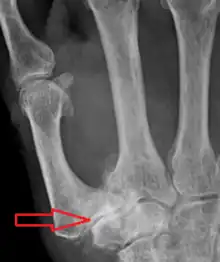

| Osteoarthritis of the trapeziometacarpal joint | |

Trapeziometacarpal osteoarthritis (TMC OA) is, also known as osteoarthritis at the base of the thumb, thumb carpometacarpal osteoarthritis, basilar (or basal) joint arthritis, or as rhizarthrosis.[3][1][2] This joint is formed by the trapezium bone of the wrist and the metacarpal bone of the thumb. This is one of the joints where most humans develop osteoarthritis with age.[4] Osteoarthritis is age-related loss of the smooth surface of the bone where it moves against another bone (cartilage of the joint).[3][5] In reaction to the loss of cartilage, the bones thicken at the joint surface, resulting in subchondral sclerosis. Also, bony outgrowths, called osteophytes (also known as “bone spurs”), are formed at the joint margins.[6]